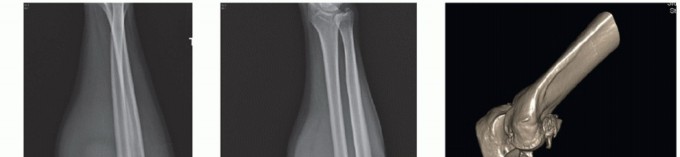

FIG 5 • A,B. AP and lateral x-ray showing a type II Monteggia fracture—posterior dislocation of radial head (or fracture) and proximal ulnar fracture with posterior angulation. C. CT scan clearly showing impaction fracture of the radial head that may not be appreciable on x-ray.*

If decision is made for operative treatment, we routinely obtain a computed tomography (CT) scan to better understand the fracture pattern for preoperative planning, so that operative time is efficient and to minimize intraoperative surprises. Three-dimensional reconstructions provide further information not always easily appreciated on routine CT scans.